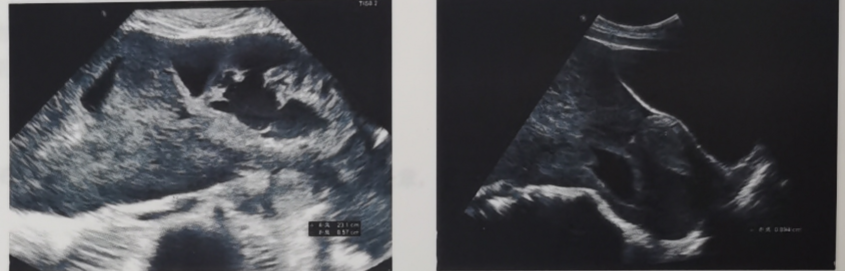

◈ 门诊行腹部超声检查提示腹盆腔巨大囊实性肿物,实性为主,范围约23.1cm×8.6cm,不规则,边界尚清,内见条形血流信号。检查提示“腹盆腔囊实性肿物,考虑间叶组织来源”。

◈ 超声介入下穿刺病理:梭形细胞肿瘤,结合形态及免疫组化结果符合胃肠间质瘤。